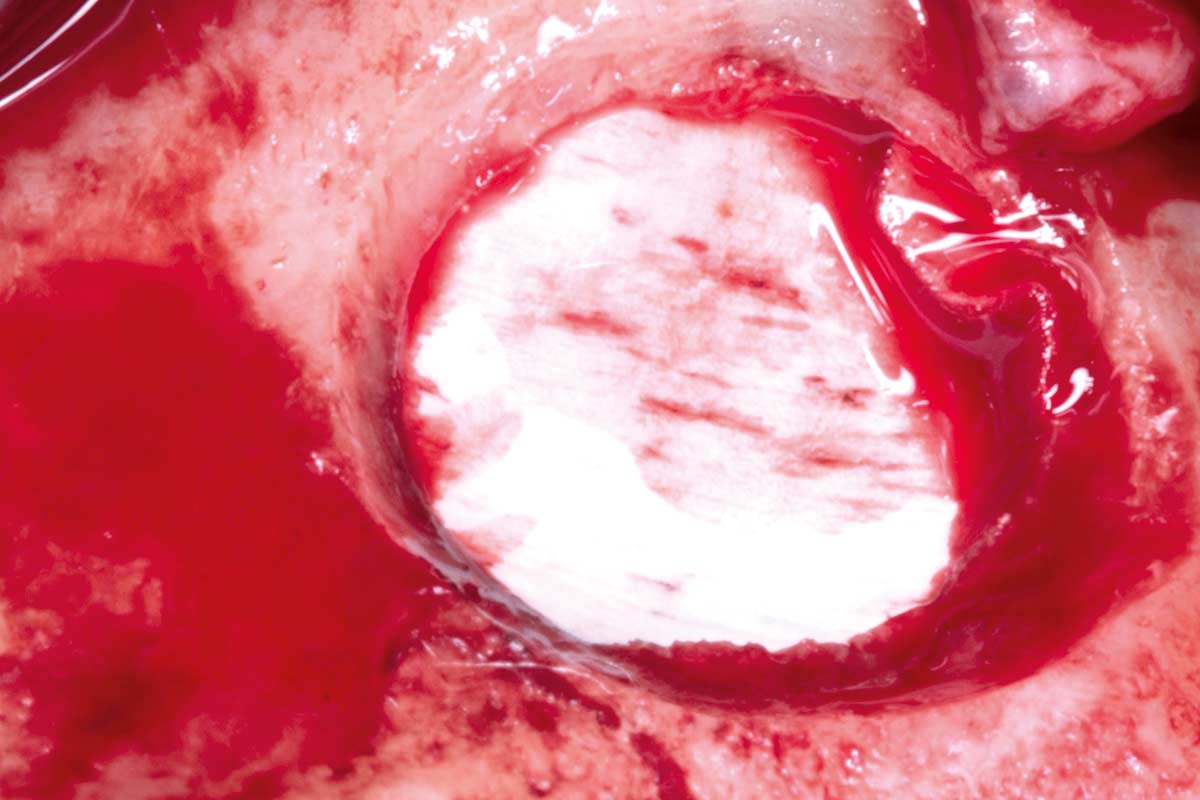

04/35 - Preparation of the lateral sinus window using piezosurgeryMaxillary sinus cyst removal using the Crocodile Technique and subsequent lateral sinus lift - Dres. C. Scognamiglio and A. Perucchi